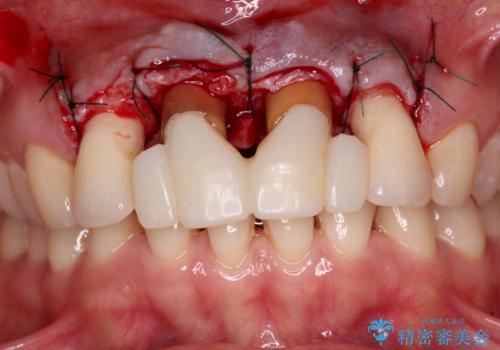

隙間をセラミックで閉じたら不格好で歯肉から出血 矯正治療と歯周外科で綺麗な前歯に

- 隙間の空いた前歯をセラミッククラウンで補隙したところ、歯肉から出血してしまい、何とかしたいとのことで来院された患者様です。

初めは前歯のみの処置で改善を希望されていたため、広範囲に処置範囲を広げることで歯の幅がバランスする治療を提案しましたが、削らなければならない歯が増えてしまうため、患者様と相談して全顎矯正により前歯のスペースを閉じていくこととしました。

不適合なクラウンが装着されていたため、歯周ポケットが深くなっていましたので、矯正治療前に歯周外科処置を行って歯周ポケットを除去し、矯正治療後にオールセラミッククラウンにて補綴治療を行うこととしました。

前歯の見た目はもちろん、出血や腫脹のない健全な前歯の状態を獲得することができました。